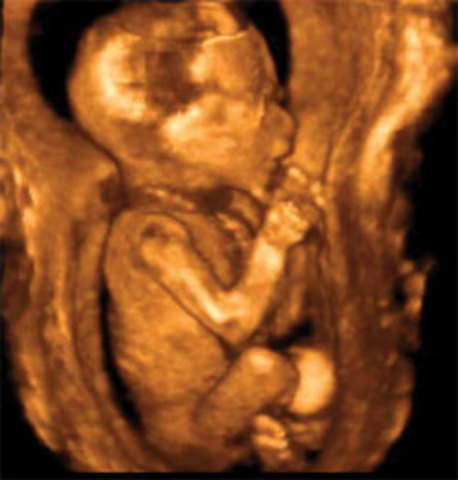

• 12 weeks

12 weeks

weighs one ounce.

• 16 weeks

16 weeks

Genital organs clearly differentiated,grasps with hands, swims,kicks,turns,somersaults, (still not felt by the mother)